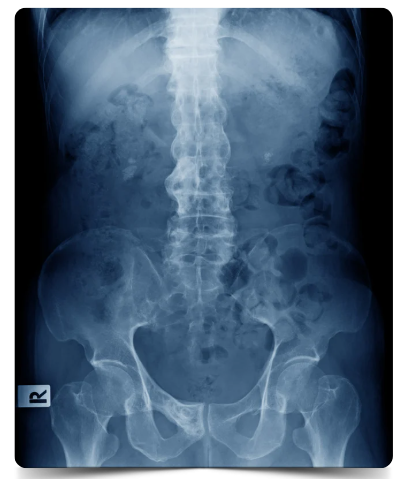

Espondiloartrite Axial é uma categoria ampla que inclui pessoas com e sem alterações ósseas características e/ou fusão na coluna vertebral. A medicina ainda classifica os adultos em um dos dois estágios que na prática clínica tem pouca relevância e de tratamento semelhante:

A Espondiloartrite Axial Radiográfica e a Não Radiográfica são, portanto, parte do mesmo espectro da doença Espondiloartrite Axial e apresentam muitos dos mesmos sintomas. A principal diferença é que aqueles com a forma não radiográfica não mostram alterações ósseas nas radiografias, embora a inflamação possa ser detectada com a ajuda da ressonância magnética. Algumas pessoas com EpAax-nr progridem para desenvolver EpAax-r, embora normalmente isso não ocorra.